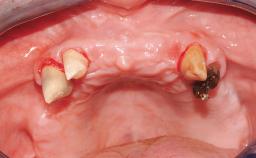

A healthy 31-year-old female patient presented with a failing maxillary left lateral incisor crown. The crown regularly loosened, and the remaining tooth was neither restorable nor rational to treat. The patient had a high smile line, a medium soft tissue biotype with a compromised mesial papilla (shorter than the contralateral one), and a horizontal scar in the buccal soft tissue as a result of past periapical surgery.

| Keratinized Tissue | Minimal (2-4 mm) |

| Soft Tissue Quality | Presence of minimal scars/no inflammation |

| Papilla | Deficient |

| Soft tissue anatomy | Soft-tissue defects |